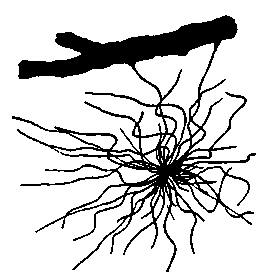

| 11. | Isolated cell from human spinal cord | 117 |

| 12. | Neuron from the optic lobe of the embryo chick | 118 |

| 22. | Motor cell of ventral horn of spinal cord from the human fetus | 133 |